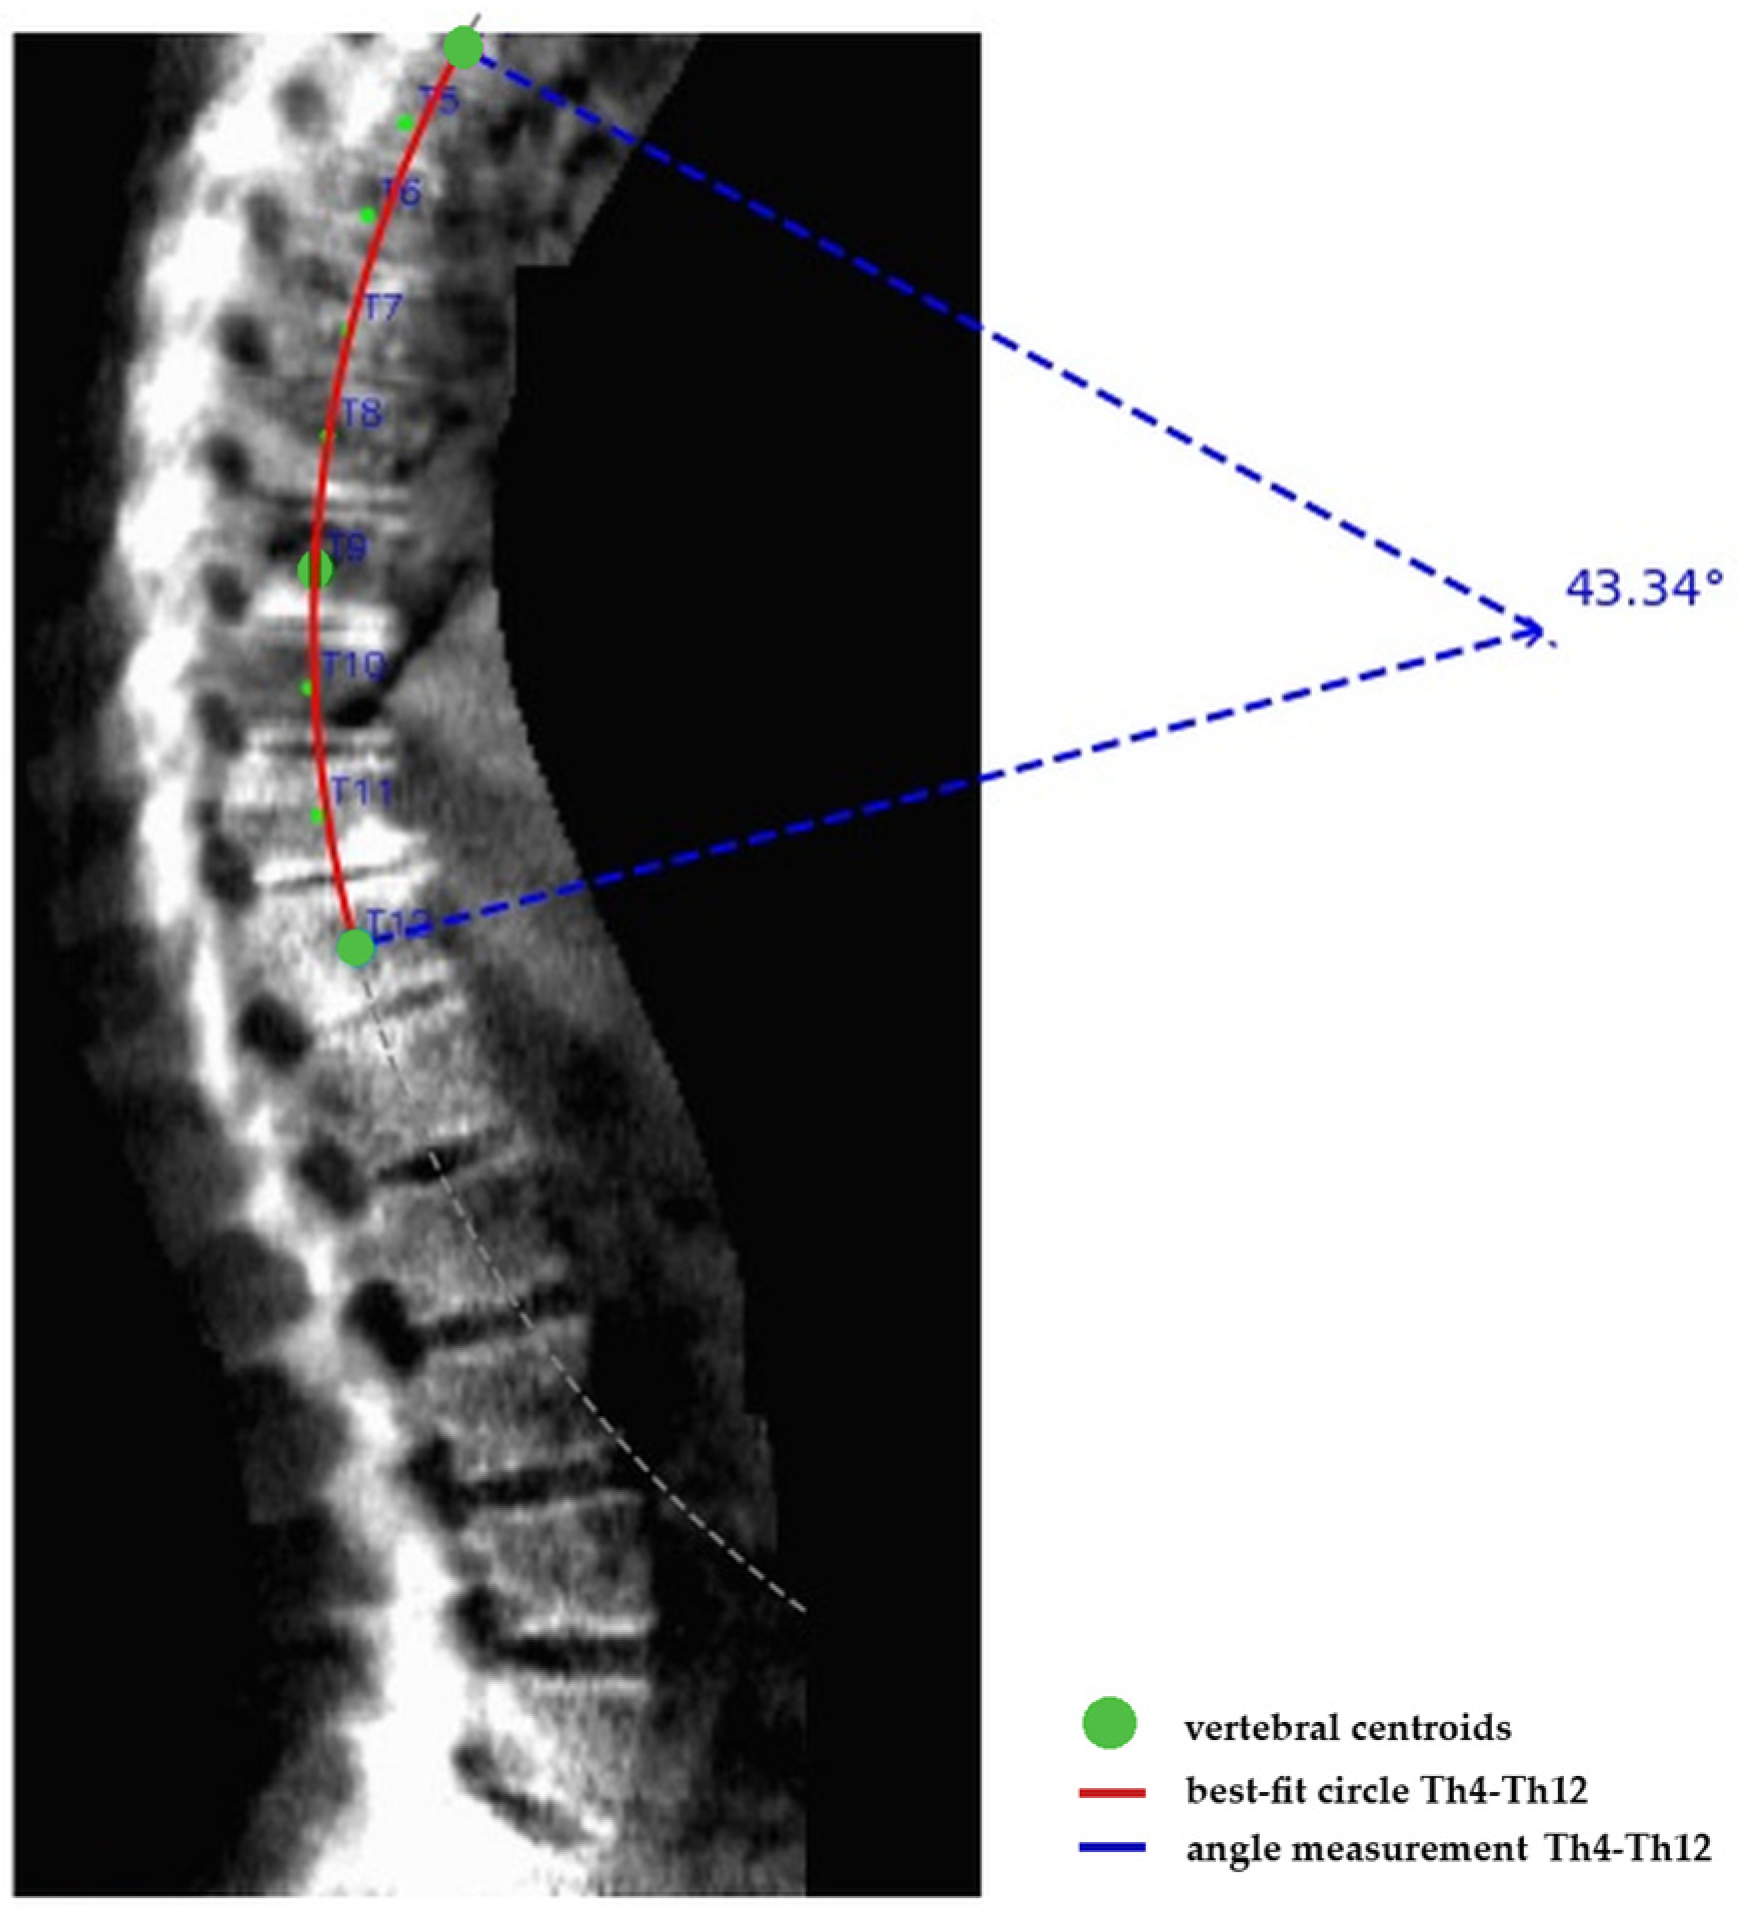

First, a geometric best-fit circle was fitted through the centroids of vertebrae Th4 to Th12 using a least-squares approach. This method provides a smooth representation of global thoracic curvature while minimizing the influence of local irregularities caused by vertebral wedging, osteophytes or minor detection noise (Figure 1).

Second, the kyphosis angle was defined as the central angle (θ) of the fitted circle, subtended by the radii connecting the circle center to the Th4 and Th12 centroids. This angle represents the arc-based curvature of the thoracic segment.

Third, the geometric central angle was converted into a clinically comparable Cobb angle using a trigonometric transformation based on the relationship between arc curvature and chord angle. Specifically, the end-to-end chord connecting Th4 and Th12 centroids was constructed and the angle between tangents at these endpoints was derived to approximate the equivalent endplate intersection angle used in Cobb measurements. This transformation ensures that the automated angle reflects the same geometric principle as the manual Cobb angle assessment, enabling direct clinical comparison.

Figure 1. Kyphosis angle from YOLO-predicted vertebral centers (Th4–Th12).